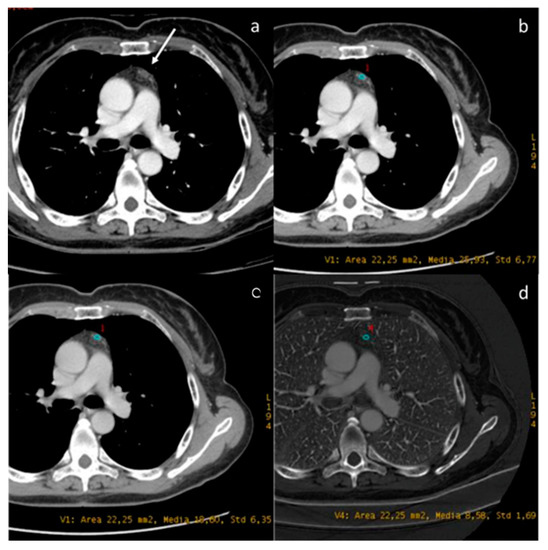

- Lennartz, S.; Le Blanc, M.; Zopfs, D.; Hokamp, N.G.; Abdullayev, N.; Laukamp, K.R.; Haneder, S.; Borggrefe, J.; Maintz, D.; Persigehl, T. Dual-Energy CT-derived Iodine Maps: Use in Assessing Pleural Carcinomatosis. Radiology 2019, 290, 796–804. [Google Scholar] [CrossRef]